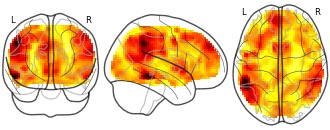

"name": "VBM_HeterogeneityMap",

"description": "Abnormal gray matter in BPD. Brain regions with significant heterogeneity (i.e. between-study variance) in the comparison of patients with BPD and healthy controls. Results are thresholded at at p<.005 & k>20. Note: Results are based on meta-analysis of group comparisons. Note2: Results were updated (see Erratum for this publication)",